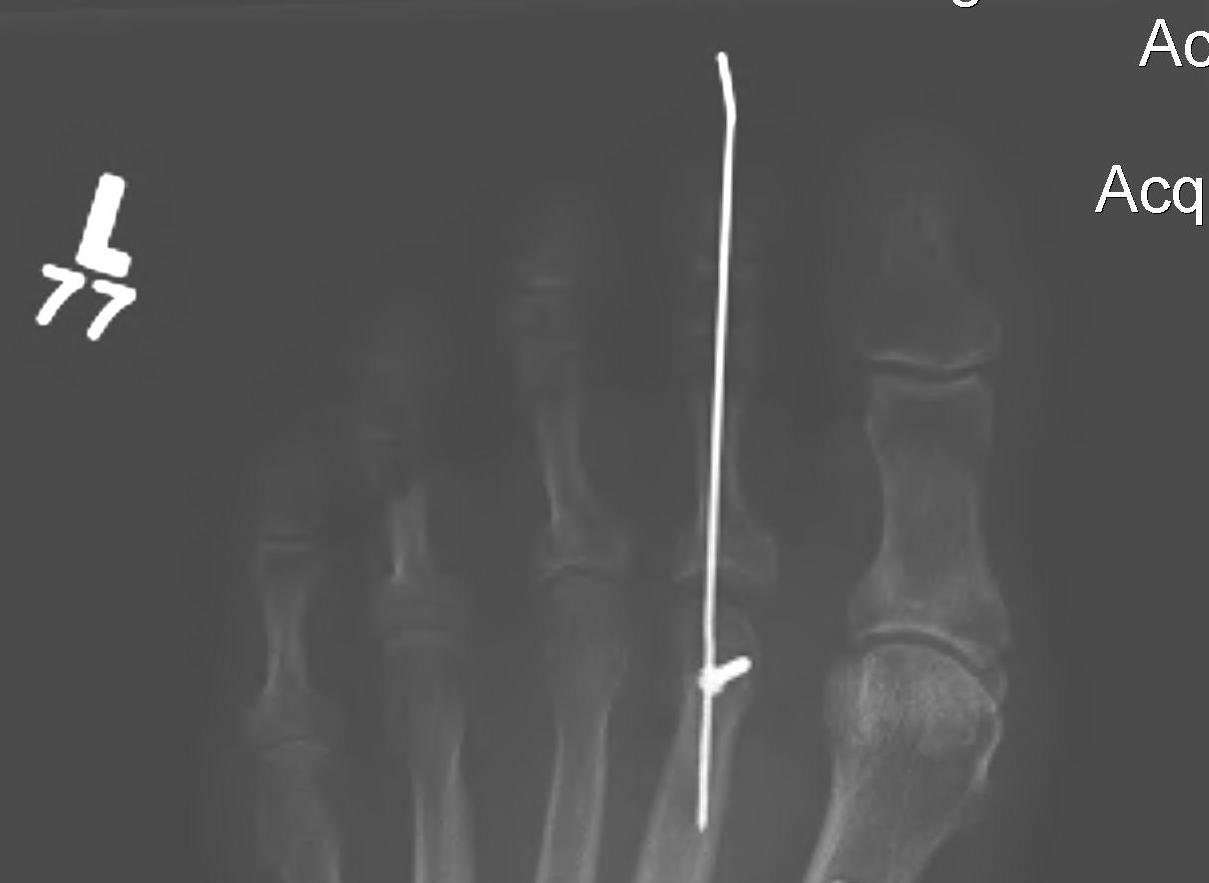

From www.semanticscholar.org

Figure 1 from Correction of Hammer Toe Deformity of Lateral Toes With Hammer Toe Osteotomy If this is the case, it can be fixed by minimally invasive. Hammer toe is a condition that affects one of the three middle toes, causing the toe to bend upward at its middle joint. Some people can manage symptoms from this condition with lifestyle. The surgery is performed to lessen pain or improve flexibility when the muscles in the. Hammer Toe Osteotomy.